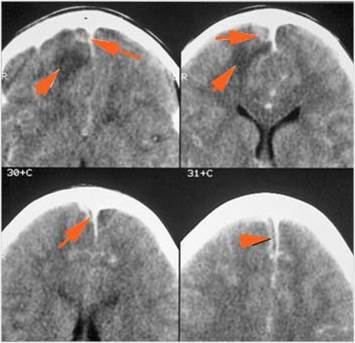

Intracranial

There is a subperiosteal fluid collection or abscess along the boney walls of the anterior or middle cranial fossa. [Yes/No]

There is an epidural fluid collection or abscess along the boney walls of the anterior or middle cranial fossa. [Yes/No]

There is a subdural fluid collection or abscess along the boney walls of the anterior or middle cranial fossa. [Yes/No]

There is a subdural fluid collection or abscess along the falx cerebri or within the tentorium. [Yes/No]

There is evidence of thrombus, thrombophlebitis or other occlusive or inflammatory process of the cortical veins, sphenoparietal sinus or sagittal sinus. [Yes/No]

There is evidence of thrombus, thrombophlebitis or other occlusive or inflammatory process of the cavernous sinus. [Yes/No]

There is evidence of inflammation of the distal internal carotid artery. [Yes/No]

There is evidence of an infectious aneurysm. [Yes/No]

There is brain edema specifically involving the frontal and temporal lobes. [Yes/No]

There is cerebritis specifically involving the frontal and temporal lobes. [Yes/No]

There is brain abscess specifically involving the frontal and temporal lobes. [Yes/No]

There is likely meningitis, meningoencephalitis with complicating hydrocephalus or brain herniation. [Yes/No]